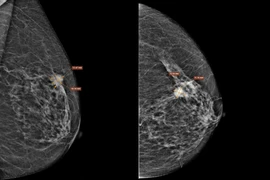

Để chẩn đoán ung thư phổi, người bệnh thường được thực hiện các xét nghiệm, chẩn đoán hình ảnh như:

- Chẩn đoán hình ảnh: CT Scanner lồng ngực; một số phương pháp chẩn đoán hình ảnh khác nhằm chẩn đoán di căn xương như CT bụng, MRI sọ - ngực, siêu âm các vị trí chẩn đoán hạch ngoại vi, chụp cắt lớp PET/CT,…